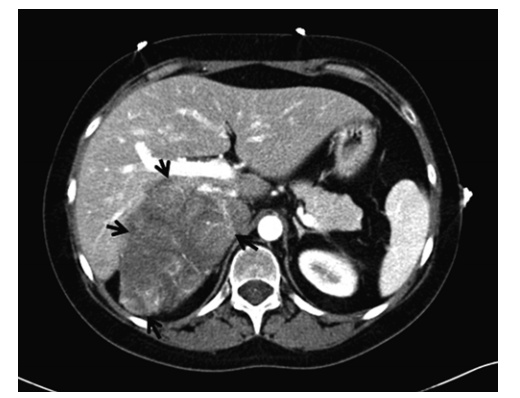

An incidentaloma is an incidentally discovered mass seen on imaging performed for an unrelated reason. Approximately 5 % of patients who undergo an abdominal CT scan will have an incidentally discovered adrenal mass. The incidence increases with patient age, with up to 10 % of patients having adrenal nodules on autopsy studies.